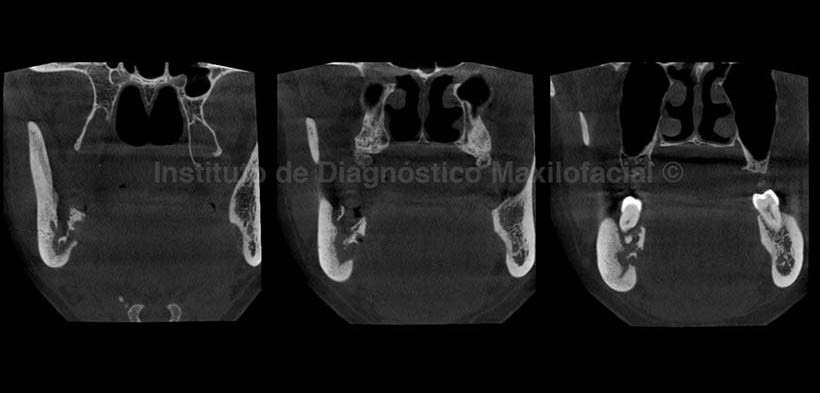

A la evaluación con Tomografía Volumétrica Cone Beam, en los cortes tangenciales (Fig. 2) se evidencia un proceso osteolítico que compromete cuerpo y rama mandibular del lado derecho; en los cortes transaxiales (Fig. 3) se observa el proceso osteolítico de la tabla ósea lingual a nivel de la pieza 4.5 y la presencia de secuestros óseos a nivel de las piezas 4.6, 4.7, con aumento de la densidad ósea circundante; así mismo, se observa un aparente compromiso de las corticales del conducto dentario inferior a nivel de dichas piezas.

En los cortes coronales (Fig.4) se aprecian ambos lados del maxilar inferior en las cuales se observa la marcada alteración del lado derecho, así como la destrucción de la tabla ósea lingual en la zona correspondiente a la pieza 4.8 la cual fue extraída algunos meses atrás. Además presenta una ligera deformación de la tabla ósea vestibular, condicionada por el aumento de la densidad ósea circundante, la cual se puede apreciar en los cortes axiales (Fig.5).